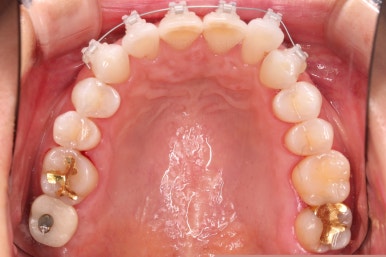

초진 시 입안의 모습입니다.

환자분이 원하셨던 부분은 윗니 작은 앞니가 하나 튀어나와서 개선하고 싶어하셨습니다.

윗니에만 장치를 부착하고 부분교정을 시작했습니다.

환자분이 연산동부분교정 선택하신 장치는 엠파워 클리어라고 하는 자가결찰 세라믹 장치입니다.

적절하게 치간삭제를 일부 동반하여 빠른 시일 내에 가지런하게 해드리고 마무리를 했습니다.

환자분이 원하시는 만큼 가지런해졌고, 부가적으로 생길 수 있는 부분들도 수용 가능한 선에서 잘 마무리가 되었습니다.